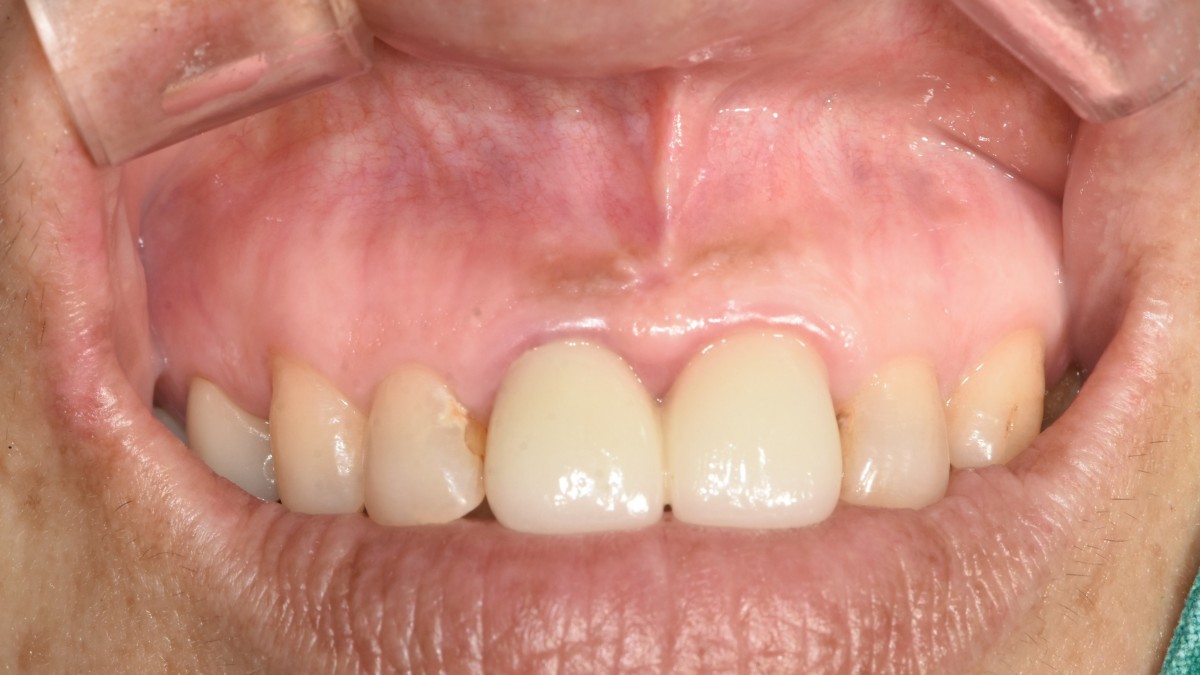

Apicorctomy /central incisor /GBR ; 6-year follow up.

<CJ SBN> Apicorctomy /central incisor /GBR ; 6-year follow up.